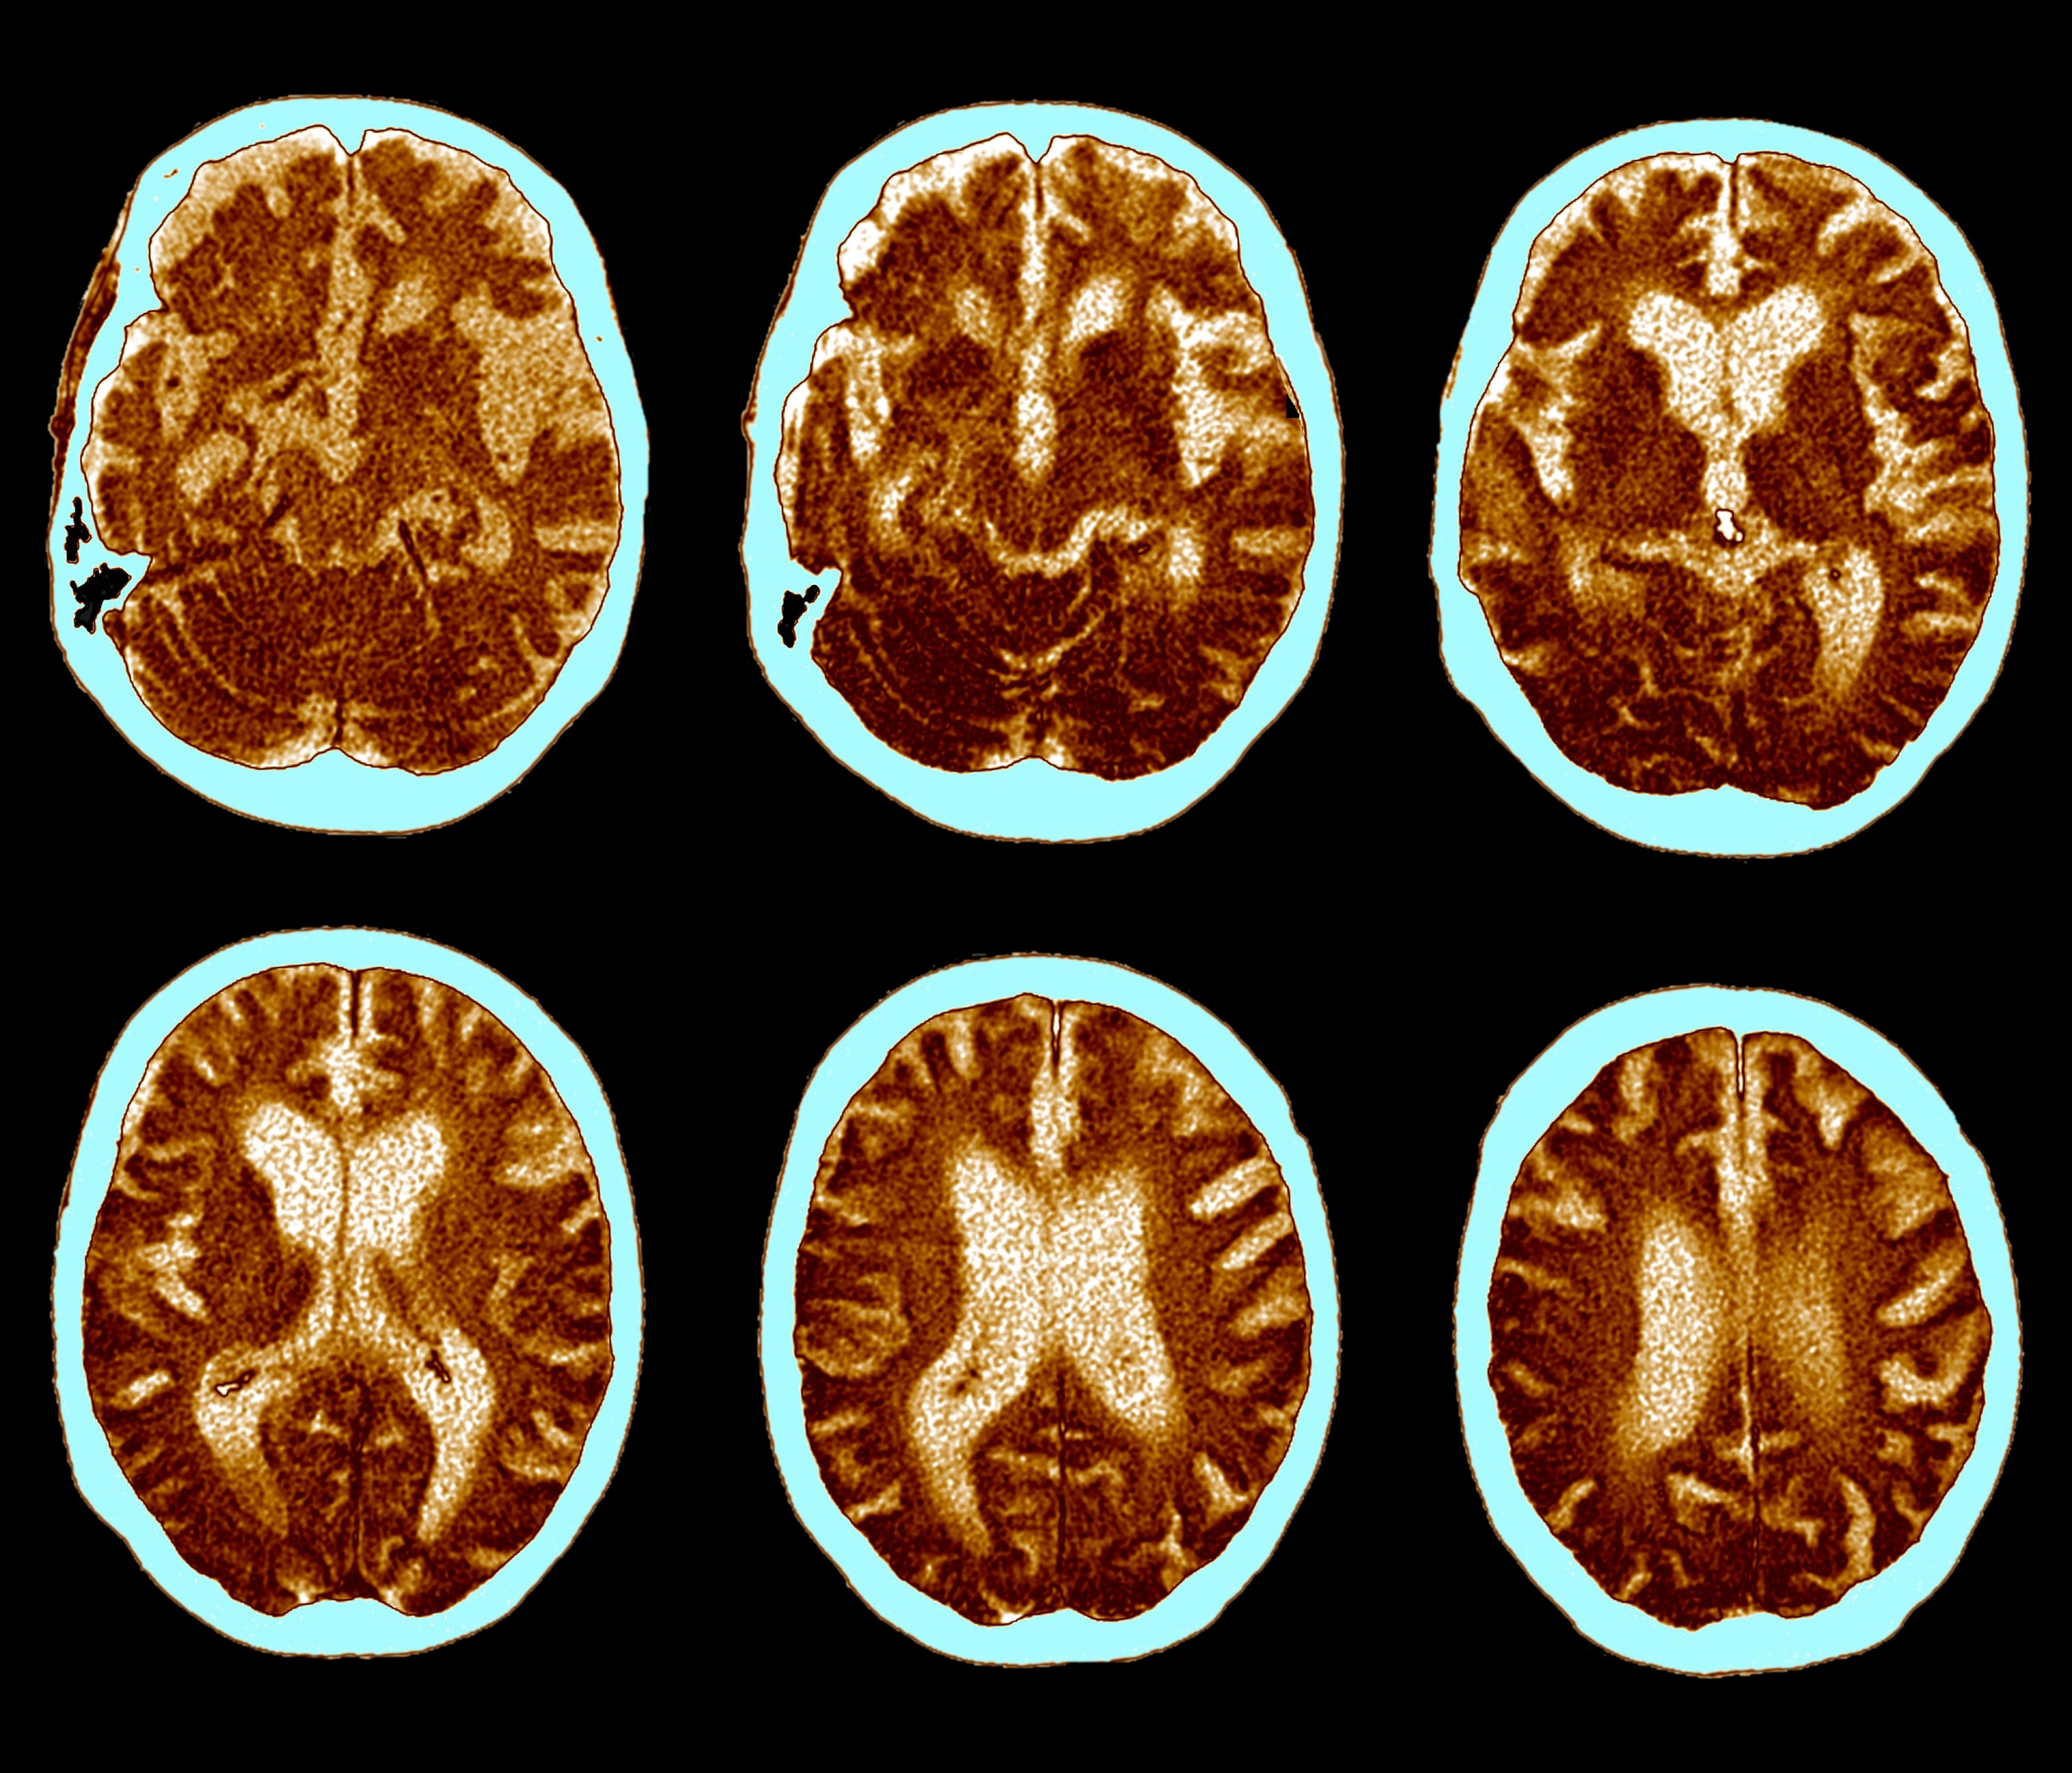

While blood samples and biopsies can somewhat illuminate understanding of disease, the intricacies of the brain make studying the chemistry, mapping the components, deciphering how neural pathways function, and detecting abnormalities in living patients highly challenging. And that makes the pursuit of therapies to treat brain diseases especially difficult.

The high failure rate, Williamson explains, is due to the fact that scientists have yet to uncover precisely what causes the disease, despite ongoing research since Alzheimer’s was first discovered in 1906. The dominant theory, he says, suggests that abnormal protein deposits form in the brain, choking off neuron activity and shrinking brain tissue. However, neuroscientists haven’t determined conclusively why these deposits start forming in the first place, or exactly what role the deposits play in the cell death that leads to Alzheimer’s memory and cognition symptoms.